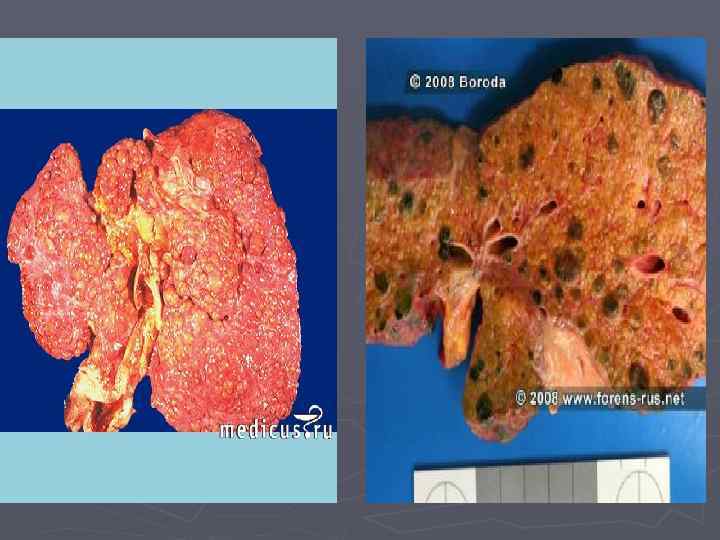

Майлы паренхималық дистрофия деп жасуша цитоплазмасында майдың көбейіп кетуін, кейде майдың қалыпты жағдайда кездеспейтін жерлерде пайда болуын немесе химиялық құрамы басқаша майлардың жиналып қалуын түсінеміз. Жасушада негізінен үшглицеридтер, холестерин эфирлері және фосфолипидтер жиналады.

Майлы паренхималық дистрофия деп жасуша цитоплазмасында майдың көбейіп кетуін, кейде майдың қалыпты жағдайда кездеспейтін жерлерде пайда болуын немесе химиялық құрамы басқаша майлардың жиналып қалуын түсінеміз. Жасушада негізінен үшглицеридтер, холестерин эфирлері және фосфолипидтер жиналады. Нәтижесінде бауырдың көрінісі мынадай болады;

Бауырдың майлы дистрофиясы Бауыр май алмасуы үрдісіне тікелей қатысатын ағза болғандықтан бұл жерде гистохимиялық реакциялар арқылы әрдайым май тамшыларын табуға болады. Сондықтан, бауырдың майлы дистрофиясы дегенде біз осы жердегі май мөлшерінің әдеттегіден көбейіп кетуын немесе химиалыық құрамы басқаша болған майлардың жиналып қалуын түсінеміз. Жасуша ішіндегі үшглицеридтер бауырдан шығып кетуі үшін апопротеин молекуласымен қосылып, липопротеин түзеді.

► Бауырдың майлы дистрофиясы улы заттар әсерінде, алкоголизмде, қантты диабетте, семіздікте, белоктық заттардың жетіспушілігіне байланысты дамиды

Май тамшылары жиналған жерлер, эндокард жағынан қарағанда ақшыл-сары түстегі жолақшалар түрінде көрінеді. Бұл көрініс «жолбарыс терісіне ұқсас жүрек» деген ат алған. Жалпы жүрек үлкейіп, қуыстары кеңіп, босап қалады. Кесіп қарағанда миокард көмескі, сарғыш-қоңыр түсте көрінеді. ► Бүйректер майлы дистрофияға байланысты үлкейіп, божырап қалады. бүйректің қыртысты қабаты қалыңдап, көмескіленіп, арасында сары түсті ұсақ бедерлер пайда болады.